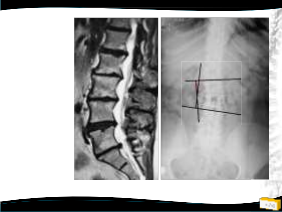

• Radyolojik değerlendirme

– Uzun kaset (26’’) filmler

• Ayakta ve yatarak

– Eğrilik (Cobb) ve fleksibite

ölçümü

– Koronal ve sagittal denge

– Spinopelvik parametreler

• PI-LL

Radyolojik bulgular

• Apeks L2 ya da L3’de

• Rotasyon, laterale kayma

(derecelendirilir)

• Genellikle oldukça fleksibl, üstte kompansatuvar eğrilik kısa ve pek az

• Lomber hipolordoz

• Osteofitler (cerrahi

planlamada önemli)